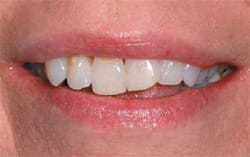

| Preoperative smile view of the patient. | Preoperative view of the patient.(View Figure) | ||||||

| Final smile view of the restored anterior dentition.(View Figure) | |||||||